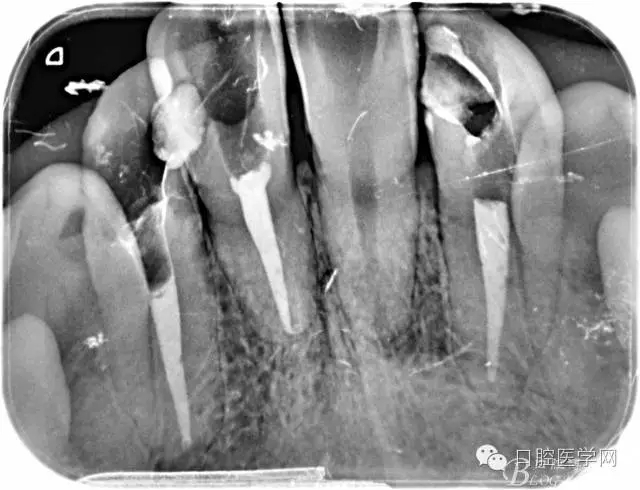

根管的解剖界限是从髓室根管入口到根尖部牙本质- 牙骨质交界处(生理性根尖孔) 。理想的根管充填应该是对生理性根尖孔冠方以上进行严密的三维封闭。临床上根据X线牙片判断根管充填的质量。牙片上充填材料与根管壁紧密接触一般被认为充填严密。关于充填止点,由于牙本质- 牙骨质界离根尖孔外表面平均距离为0. 5~0. 7 mm,同时相当多的根尖开口并不位于X线片的根尖处。因此临床上认为材料充填至距X线片牙根最尖端0. 5~1 mm (也有认为0. 5~2mm)为适填。

为达到更为理想的根充效果,研究人员和牙髓病医生一直在探索根管充填技术,并且发展出多种可供选择的方法。Ingle]将其归纳为3 类: ①“牙胶尖+封闭剂”式; ②“根尖1 /3充填”式; ③“注射或螺旋充填”式。目前临床广泛采用的主要是“牙胶尖+封闭剂”方式。按照充填压力的方向(侧向或垂直)不同和牙胶温度(冷或热)不同,根管充填有2 种基本技术:冷牙胶侧方加压充填和热牙胶垂直加压充填。现有的各种充填方法均是这2 种基本方法基础上的发展或改良。医生可根据方法的优缺点以及个人习惯选择使用。

6、封闭剂使用